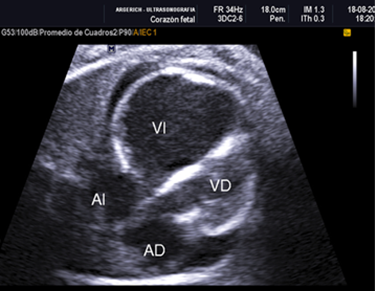

Por tal hallazgo se solicita ecocardiografía fetal a la unidad de Medicina fetal que reporta:1) Engrosamiento hiperecogenico endocárdico del ventrículo izquierdo dilatado con disfunción diastólica severa, motilidad ventricular casi ausente compatible con fibroelastosis endocárdica (Figura Nº1). 2) Desviación del tabique interventricular al lado derecho con dos comunicaciones interventriculares pequeñas cerca del ápex. 3) Derrame pericárdico de 3 mm en relación a la pared posterior del VI. 4) tractos de salida y entrada normales. También se solicita Doppler obstétrico observándose hemodinamia feto-placentaria y útero-placentaria normal (Figura 1).

Figura 1 Dilatación de ventrículo izquierdo con engrosamiento hiperecogénico subendocárdico con severa disfunción contráctil y derrame pericárdico